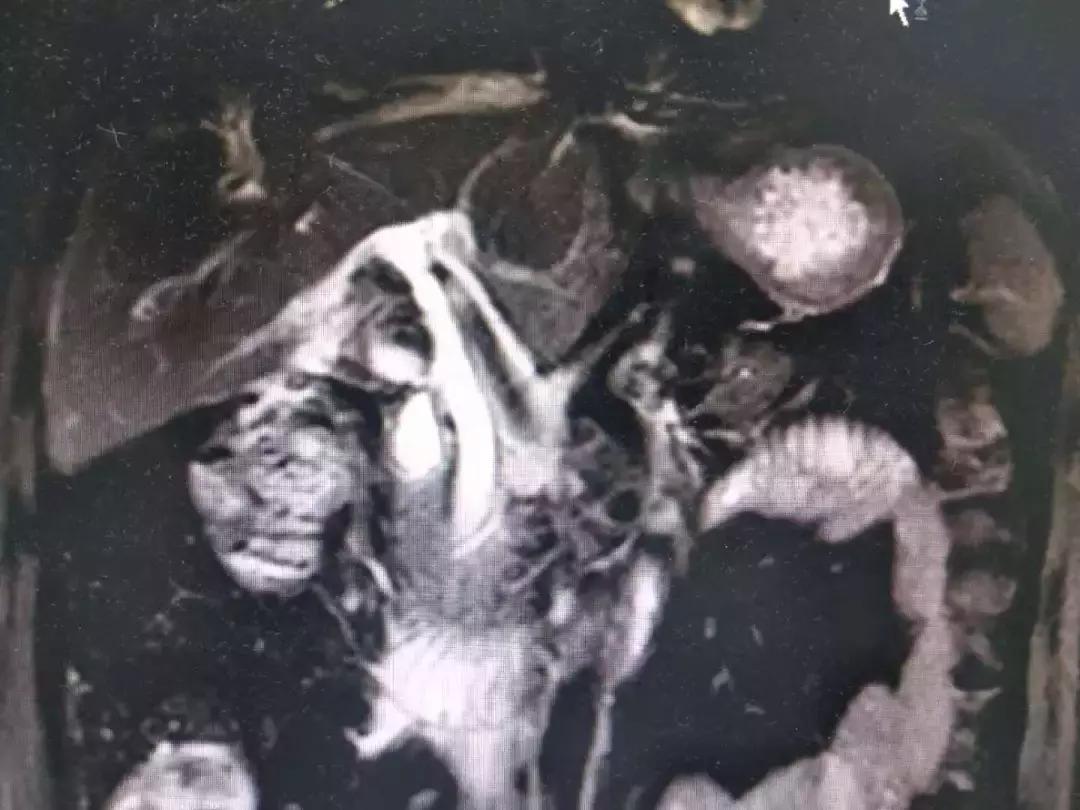

患者因持续上腹疼痛伴高热黄疸1天入院,患者1天前因上腹痛伴发热在其他医院就诊,查腹部CT提示胆囊结石,胆囊炎,胆总管结石,胆总管扩张,并出现黄疸,患者未行手术治疗,腹痛黄疸发热加重,后就诊于我院。入院后,普外科在左富义主任团队的带领下详细询问病史,完善MRCP检查,发现胆总管多发结石引起急性梗阻性化脓性胆管炎,梗阻性黄疸,需急诊手术治疗解除胆道梗阻,左主任组织科内进行术前讨论,充分完善术前准备,术前给予补充维生素、改善凝血功能,抗炎营养支持等治疗。于8月21日在左富义主任指导下,由石世华副主任、张锦秀副主任医师及张芮浦医师在气管插管全麻下实施腹腔镜、胆道镜联合胆总管切开探查取石、胆囊切除、T管引流术,手术顺利,术后给予抗炎、营养支持、中药导入、保肝退黄等治疗,患者术后次日恢复饮食,T管引流通畅,腹腔引流管已拔除,体温及肝功能恢复正常,痊愈出院。

胆总管结石是临床常见疾病,病情通常变化快,常引起肝功能进行性损害及急性梗阻性化脓性胆管炎,后期可引起感染性休克、肝脓肿、肝功能衰竭危及患者生命,需要限期甚至急诊进行手术治疗,有效解除梗阻,方可改善肝功能、凝血功能,感染多能在梗阻解除后得到有效控制。因结石梗阻部位特殊,目前手术治疗方案有开腹胆总管切开探查取石、胆囊切除、T管引流,ERCP检查十二指肠乳头切开取石(EST)、鼻胆管引流术(ENBD),然后再行胆囊切除术,此外还可行腹腔镜联合胆道镜胆总管切开探查取石,胆囊切除术。开腹手术创伤较大,住院时间长,需要较长时间留置T管;ERCP内镜下行EST取石有手术成功率不高以及取石术后继发反流性胆管炎及十二指肠乳头因切开后导致狭窄等远期并发症,治疗费用昂贵,普及率不高。